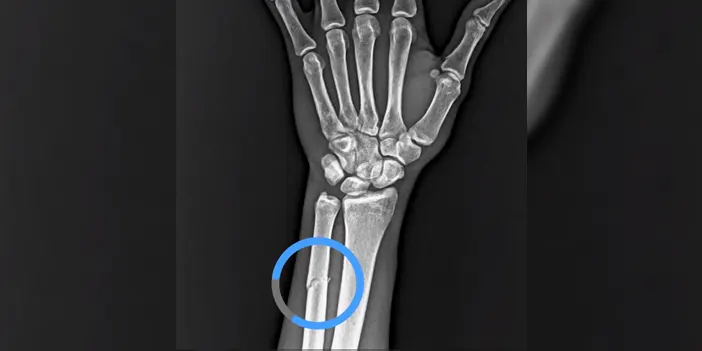

Trabzonspor’un Ziraat Türkiye Kupası Çeyrek Finalinde Başakşehir ile oynadığı karşılaşmada Paul Onuachu sakatlanarak oyundan çıkmıştı.

Bordo mavili takımın dev oyuncusu hakkında ilk kez Haber61, kolunda kırık tespit edildiğini yazmıştı. Trabzonspor tarafından yapılan paylaşımda golcü oyuncunun röntgen görüntüsü paylaşıldı.

İŞTE O GÖRÜNTÜ